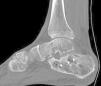

Mala consolidación tipo II: exostosis lateral prominente y artrosis subastragalina (fig. 9). Tratamiento mediante exostectomía lateral, tenólisis de peroneos y artrodesis subastragalina con injerto estructural en bloque (figs. 10 y 11).

Mala consolidación tipo III: exostosis prominente, artrosis subastragalina y mala alineación del retropié mayor a 10°. Tratamiento mediante exostectomía, tenólisis de peroneos, artrodesis subastragalina con injerto en bloque (artrodesis y distracción) además de osteotomía de calcáneo (varizante o valguizante).